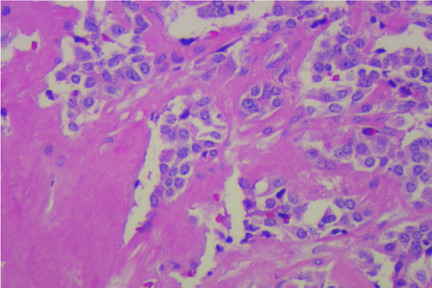

Fig. 3 H&E |

Medullary Carcinoma of Thyroid (Figure 3)

Medullary carcinoma of the thyroid is an uncommon malignancy of the thyroid that tends to differentiate similar to the C-cells. The cells have the typical neuroendocrine appearance similar to carcinoid or neuroendocrine tumors of the pancreas with speckled chromatin (so-called “salt & pepper” chromatin) and a plasmacytoid to spindle cellular shape. They tend to secrete calcitonin which can be a useful ancillary monoclonal IP test as compares to papillary or follicular carcinoma of the thyroid that will be thyroglobulin positive and calcitonin negative. They are also associated with amyloid production that may be identified on FNA smears as amorphous background material but more often visible on the histology. Amyloid is Congo-Red stain positive with apple green birefringence when polarized but proper, even thickness is rarely obtainable on direct smears. Thus Congo Red staining may be less predictable than IP staining for cytology specimens. IP staining may also be performed on a smaller specimen quantity.